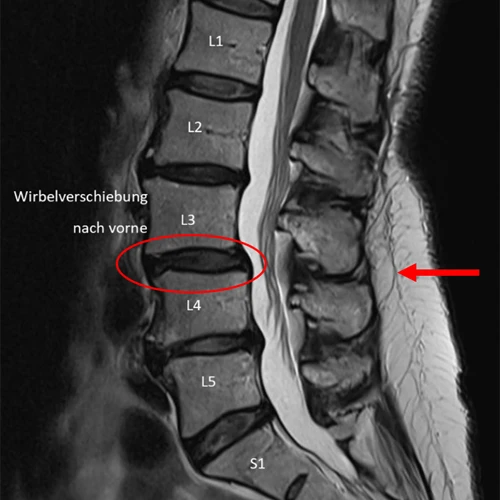

Vergleich Medi Mouse Messung mit MRI

1. Beispiel – Wirbelverschiebung nach vorne

Vergleicht man die Messung der Medi Mouse mit der MRI-Aufnahme der Lendenwirbelsäule der gleichen Patientin, kann man erkennen, dass die Höhe der Knickstellung, welche ihre Ursache in der Wirbelverschiebung nach vorne hat, beim gleichen Segment detektiert wurde.

Wirbelverschiebung Medi-Mouse

Wirbelverschiebung MRI